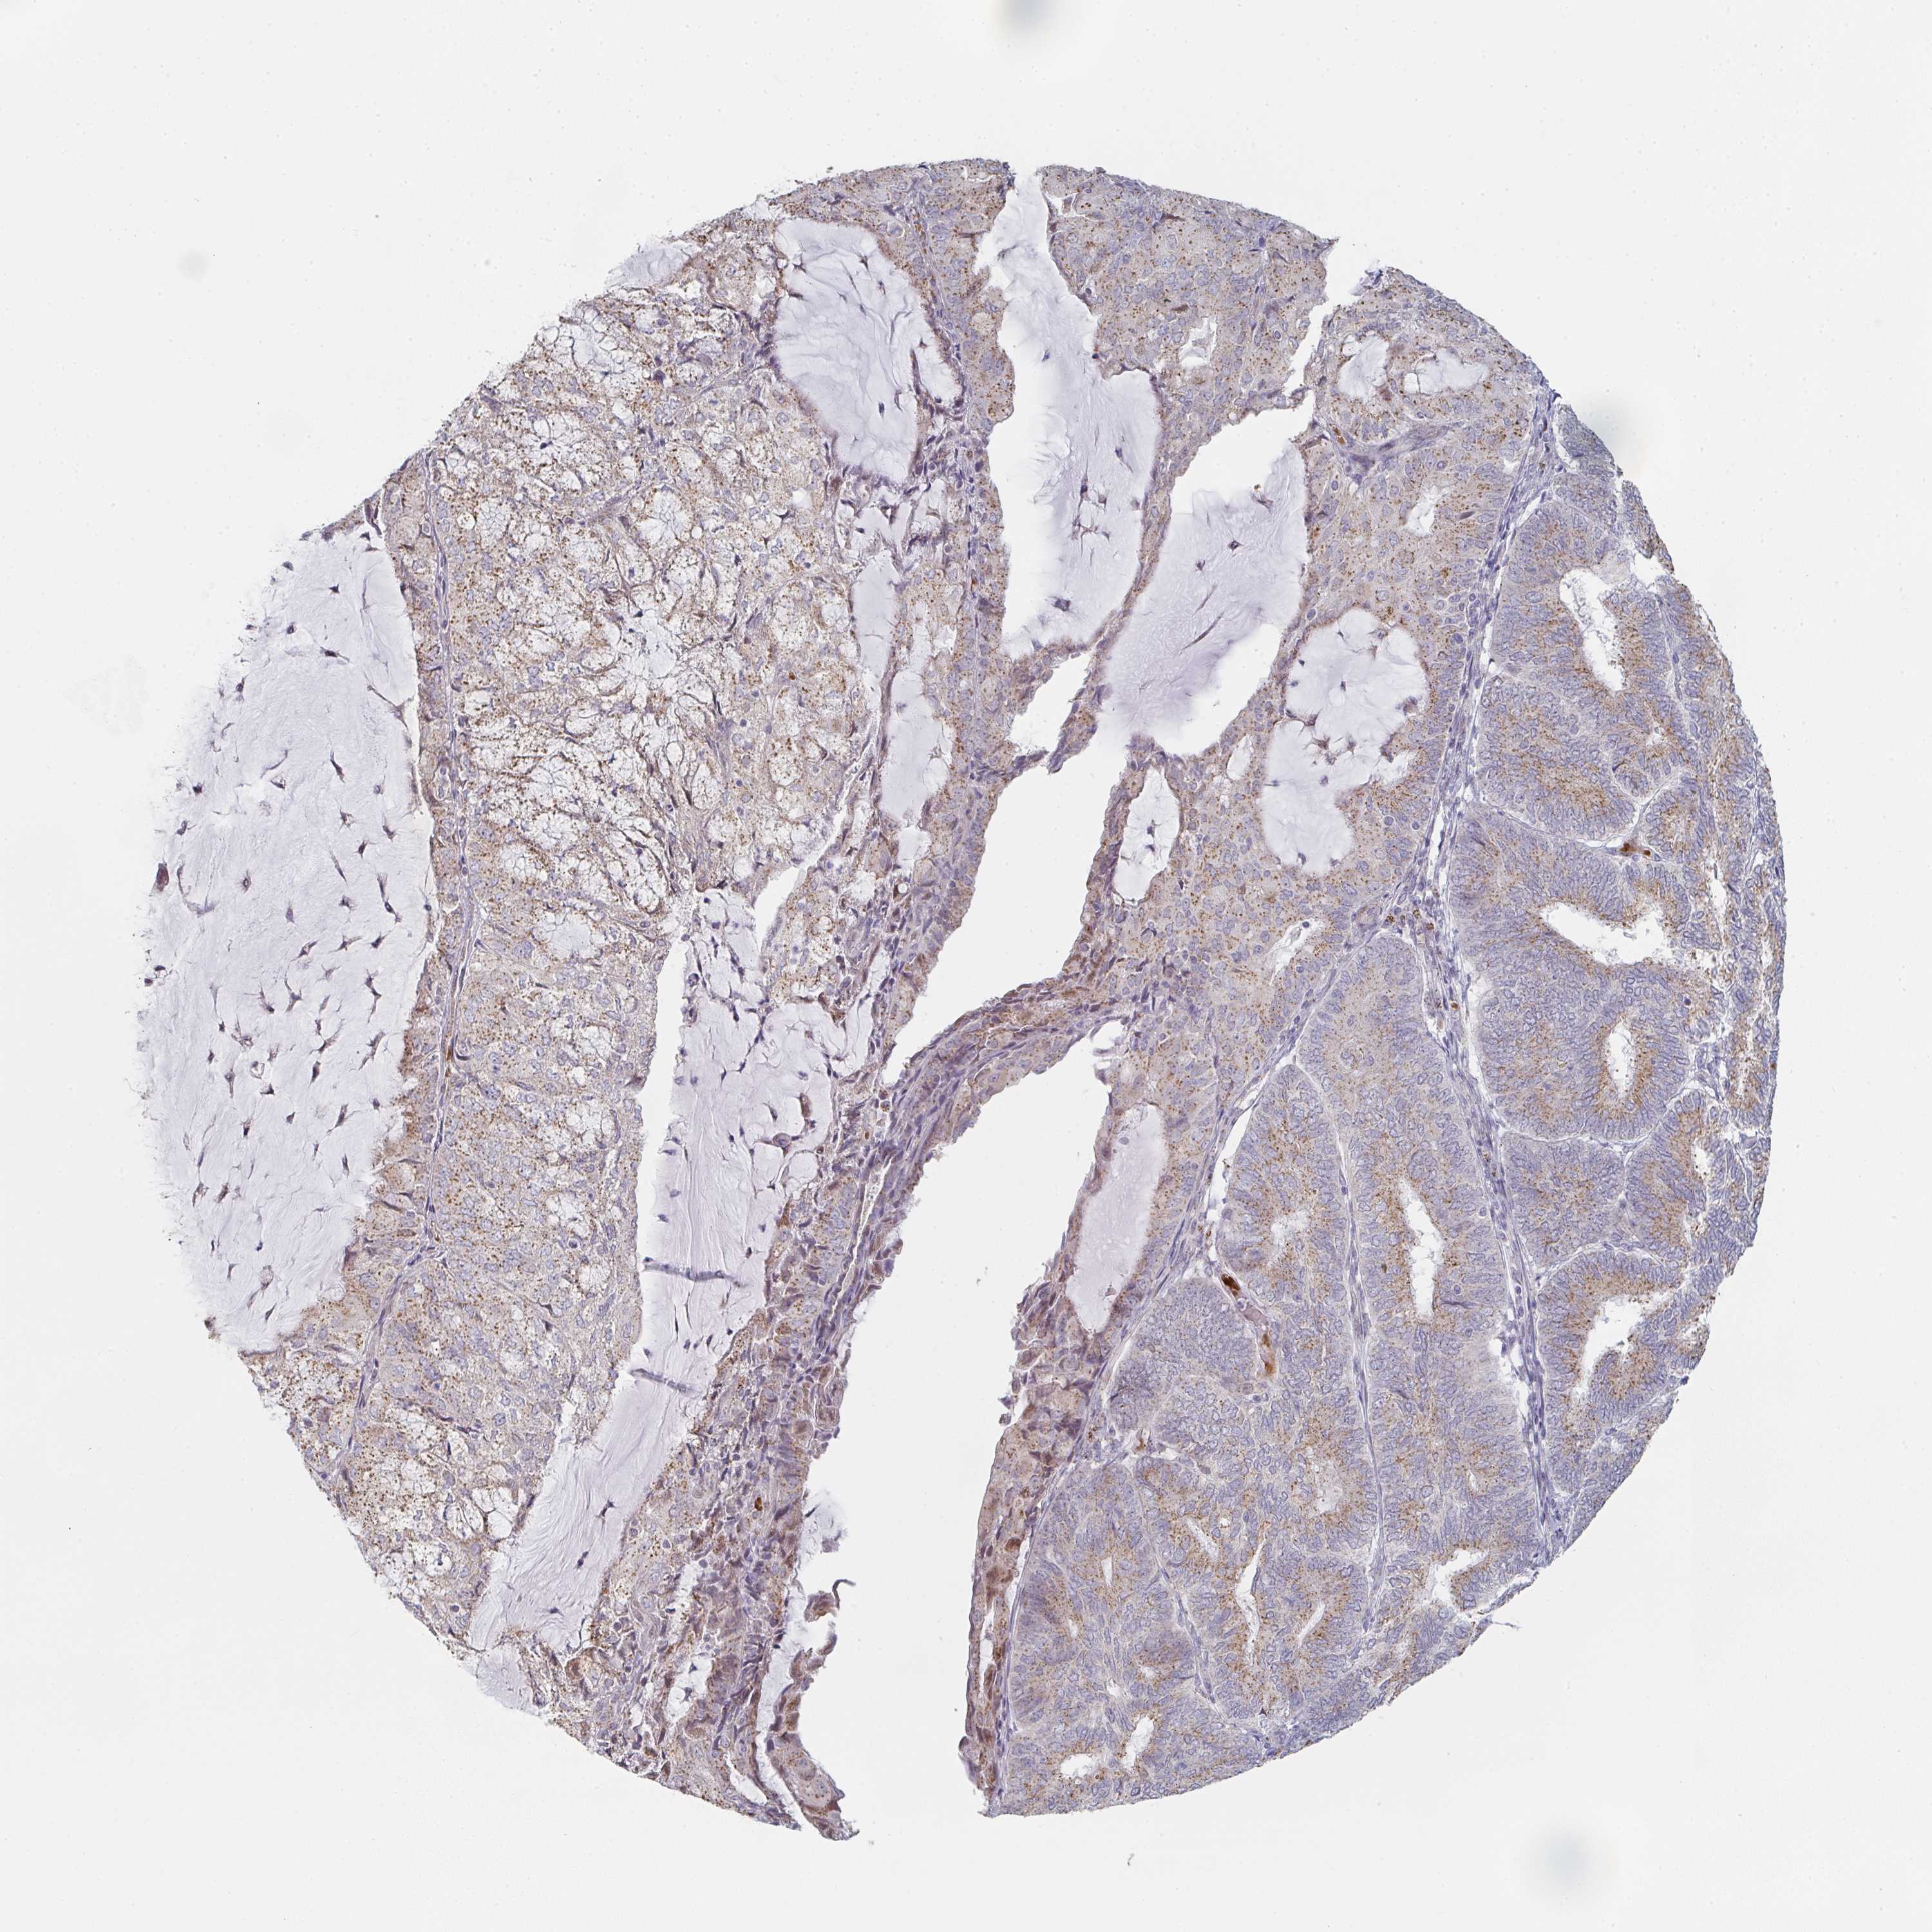

ENDOMETRIAL CANCER - Protein expressioni

A mouse-over function shows sample information and annotation data. Click on an image to view it in a full screen mode. Samples can be filtered based on level of antibody staining by selecting one or several of the following categories: high, medium, low and not detected. The assay and annotation is described here.

Note that samples used for immunohistochemistry by the Human Protein Atlas do not correspond to samples in the TCGA dataset.

Antibody stainingi

Antibody staining in the annotated cell types in the current human tissue is reported as not detected, low, medium, or high, based on conventional immunohistochemistry profiling in selected tissues. This score is based on the combination of the staining intensity and fraction of stained cells.

Each image is clickable and will lead to virtual microscopy that enables deeper exploration of all samples and also displays staining intensity scores, fraction scores and subcellular localization as well as patient and tissue information for each sample.

Antibody HPA023070

Antibody HPA056609

Staining

High

Medium

Low

Not detected

Intensity

Strong

Moderate

Weak

Negative

Quantity

>75%

75%-25%

<25%

None

Location

Nuclear

Cytoplasmic/membranous

Cytoplasmic/membranous,nuclear

Adenocarcinoma, NOS